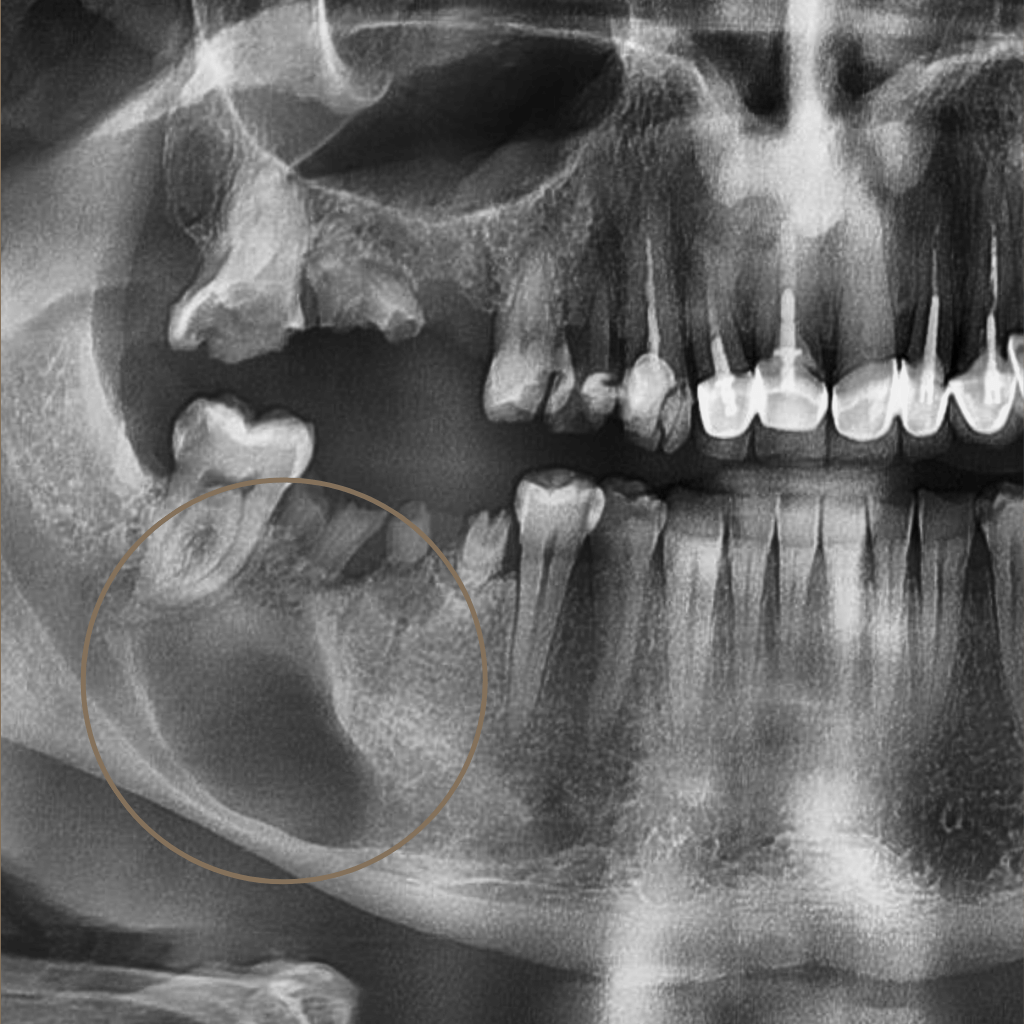

Промени в костта или меките тъкани на лицево-челюстната област изискват прецизна диагностика и ясен терапевтичен план. Навременното установяване на характера на лезията е ключово за правилното лечение и прогнозата.

В лицево-челюстната област туморите и кистите могат да засегнат костните структури, венците, езика, бузите и други тъкани на устната кухина. В клиничната практика се срещат както доброкачествени образувания, така и предтуморни или злокачествени състояния, които изискват навременна и точна диагностика.

Извършва се клиничен преглед и анализ на образните изследвания, за да се оцени локализацията, обемът и характерът на формацията.

• Неясни находки при образни изследвания